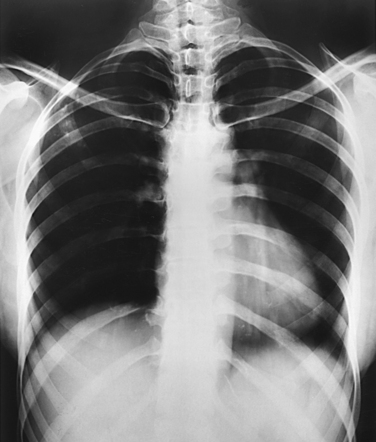

The position of the diaphragm varies with body habitus: It is at a higher level in hypersthenic patients and at a lower level in asthenic patients (Fig. 9-9). In sthenic patients of average size and shape, the right side of the diaphragm arches posteriorly from the level of about the 6th or 7th costal cartilage to the level of the 9th or 10th thoracic vertebra when the body is in the upright position. The left side of the diaphragm lies at a slightly lower level. Because of the oblique location of the ribs and the diaphragm, several pairs of ribs appear on radiographs to lie partly above and partly below the diaphragm.

Fig. 9-9 Diaphragm position and body habitus. A, A hypersthenic patient has a diaphragm positioned higher. B, An asthenic patient has a diaphragm positioned lower. C, Chest radiograph of a hypersthenic patient. D, Chest radiograph of an asthenic patient. Note position of diaphragm on these extremely different body types.

The position of the diaphragm changes considerably with the body position, reaching its lowest level when the body is upright and its highest level when the body is supine. For this reason, it is desirable to place the patient in the upright position for examination of the ribs above the diaphragm and in a recumbent position for examination of the ribs below the diaphragm.